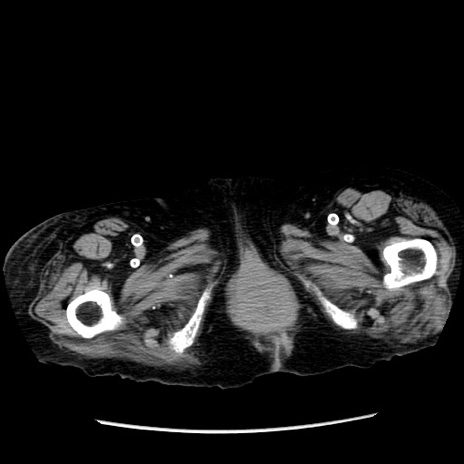

症例14(横断像)

【症例】 90歳代女性

【主訴】 腹痛・嘔吐

【現病歴】今朝から左側腹部痛を認めた。 経過観察していたが、嘔吐を認めたため来院。

【既往歴】 子宮癌術後

【身体所見】 意識清明、BP 127/54mmHg、P 98bpm Sp02 95%(RA)、BT 35.8°C、腹部平坦・軟腸ぜん動音聴取良好、右下腹部圧痛(+) 反跳痛なし

【データ】WBC 9800、CRP 0.46